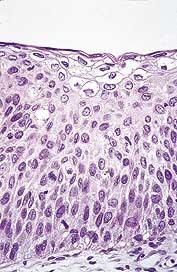

Siden viruset ikke kan dyrkes i vevskultur, må det påvises med lysmikroskopi (fig 1), identifikasjon av proteiner eller HPV-gensekvenser i det infiserte vevet (fig 2). Pågående eller gjennomgått HPV-infeksjon vil også føre til antistoffstigning i blodet, noe som kan påvises med forskjellige serologiske assays.

E4-genet koder for proteiner som uttrykkes sent i virusets livssyklus. E4 induserer forandringer i intracellulær matriks som gjør at virus lettere frigjøres fra cellen (27, 28). Disse forandringene fører til koilocytose, som er en av de mest karakteristiske lysmikroskopiske kjennetegn på en HPV-infeksjon. Koilocyttene har, i motsetning til østrogenstimulert plateepitel, forstørrede og hyperkromatiske cellekjerner med uregelmessig kjernekontur og perinukleær oppklaring i cytoplasma. De påvises i det superfisielle cellelag i plateepitelet (fig 1, fig 2).